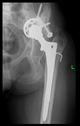

The guiding wire was inserted and controlled with fluoroscopy flashes (Figure 4). The drilling and reaming were carried out in accordance with the recommendations:

Figure 4.

The biocompatible aiming device after insertion of the guiding wire.

The direction of the cup stem was determined by the guide wire. The aiming device was needed to introduce this wire. After removing the aiming device, the next step was the drilling. Since a cannulated drill bit was used, the previously installed wire could guide the process. A self-positioning reaming tool was then used in the drilled channel. In the prepared cavity, the cup was fitted perfectly. Of the two stemmed cups available to us, the McMinn cup (Waldemar Link, Hamburg, Germany) had the simpler geometry and was therefore chosen. The stemmed cup was inserted according to the manufacturer’s recommendation. In the presence of a significant bone defect, a synthetic bone graft may be impacted for substitution.